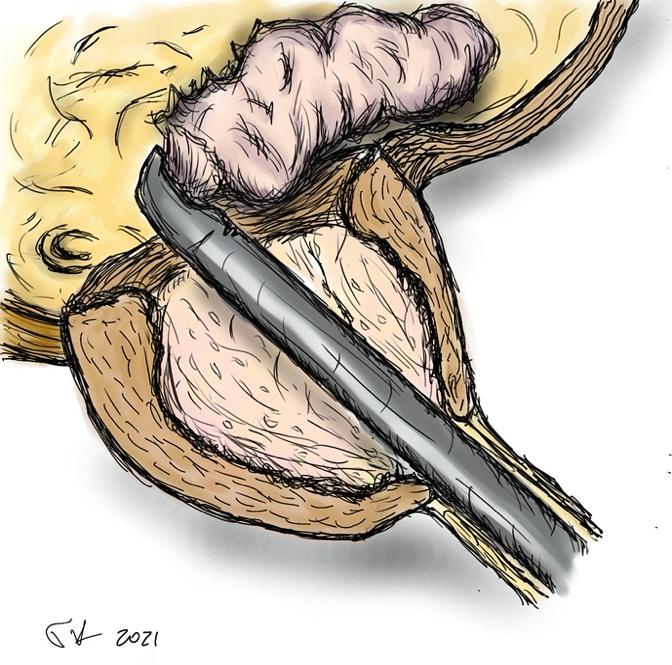

- το προστατικό αδένωμα αποκολλάται από την κάψα με τη βοήθεια του ειδικού ηλεκτροδίου εκπυρήνισης (εικόνες 1-4)

Εικόνες 1-4